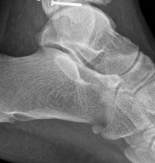

Fluoroscopic Verification

Before closure, comprehensive fluoroscopic imaging is mandatory. True AP and lateral views, along with oblique projections, are obtained to confirm anatomic reduction of the joint line, verify restoration of mechanical alignment, and ensure that no hardware has penetrated the intra-articular space.